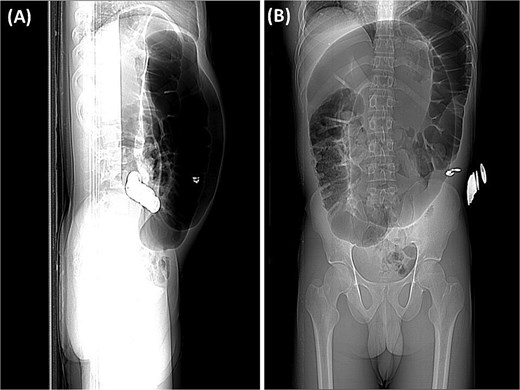

Abdominal radiography demonstrated classic features of sigmoid volvulus including dilated colonic loops, multiple air-fluid levels, and the characteristic coffee bean sign with absence of rectal gas. Computed tomography (CT) imaging (Figs 1 and 2) confirmed the diagnosis, revealing large gas-filled loops (maximum diameter 100 mm) without haustration and the typical mesenteric whirl sign, consistent with closed-loop obstruction. Initial management with colonoscopic decompression was attempted but proved unsuccessful, with persistent abdominal distension and tympani necessitating surgical intervention. Intraoperative findings confirmed a dolichosigmoid with mesenterico-axial volvulus, requiring sigmoid colon resection with creation of a double-barrel stoma using the Bouilly-Volkmann technique. Pathological examination of the resected specimen (30 cm in length, 491 g in weight) revealed flattened, hemorrhagic mucosa with vascular congestion and edema (Fig. 3). Microscopic analysis identified numerous Schistosoma eggs of varying morphology (Fig. 4A and B) within the submucosa and muscular layers, accompanied by granulomatous inflammation (Fig. 4C) and dense eosinophilic infiltrates. Chronic changes including eosinophilic microabscesses and calcified eggs were also noted (Fig. 5).

Axial abdominal CT scan revealed dilated gas-filled loops with lack of the haustration.